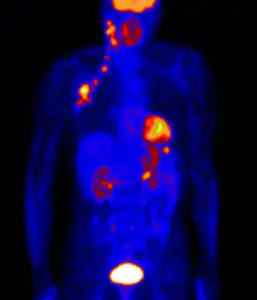

การตรวจหามะเร็งตับเอกซเรย์คอมพิวเตอร์ (CT scan)

การตรวจเอกซเรย์คอมพิวเตอร์ (CT scan)

เป็นการตรวจที่รวมกันระหว่างการตรวจเอกซเรย์คอมพิวเตอร์กับการตรวจพิเศษด้านเวชศาสตร์นิวเคลียร์ที่เรียกว่า PET Scan มีการฉีดสารชนิดหนึ่งที่เป็นน้ำตาล ที่เรียกว่า FDG ซึ่งจะไปจับตัวอยู่ตรงบริเวณที่เป็นมะเร็ง แล้วเราสามารถสแกนภาพจากเอกซเรย์คอมพิวเตอร์ออกมาได้ ทำให้มีความจำเพาะและเชื่อถือได้สูง หากผลการตรวจพบว่า มีการจับตัวของ FDG ในตัวก้อนเนื้อ แต่หากตรวจแล้วไม่มีการจับตัวของ FDG ก็มิได้หมายความว่าจะไม่ได้เป็นมะเร็ง มีผู้ป่วยมะเร็งตับเพียง 50% เท่านั้น ที่ตรวจด้วยวิธีนี้ แล้วมีการจับตัว เราจึงไม่ได้นำวิธีนี้มาใช้ในการวินิจฉัยโรคเบื้องต้น แต่มักใช้ในการติดตามผลการรักษามากกว่า